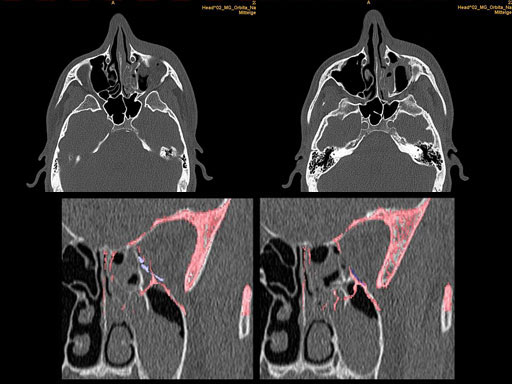

30 year old male patient with fracture of left orbital floor and medial wall.

Provided by Dr Dr Marc C Metzger, Freiburg, Germany.